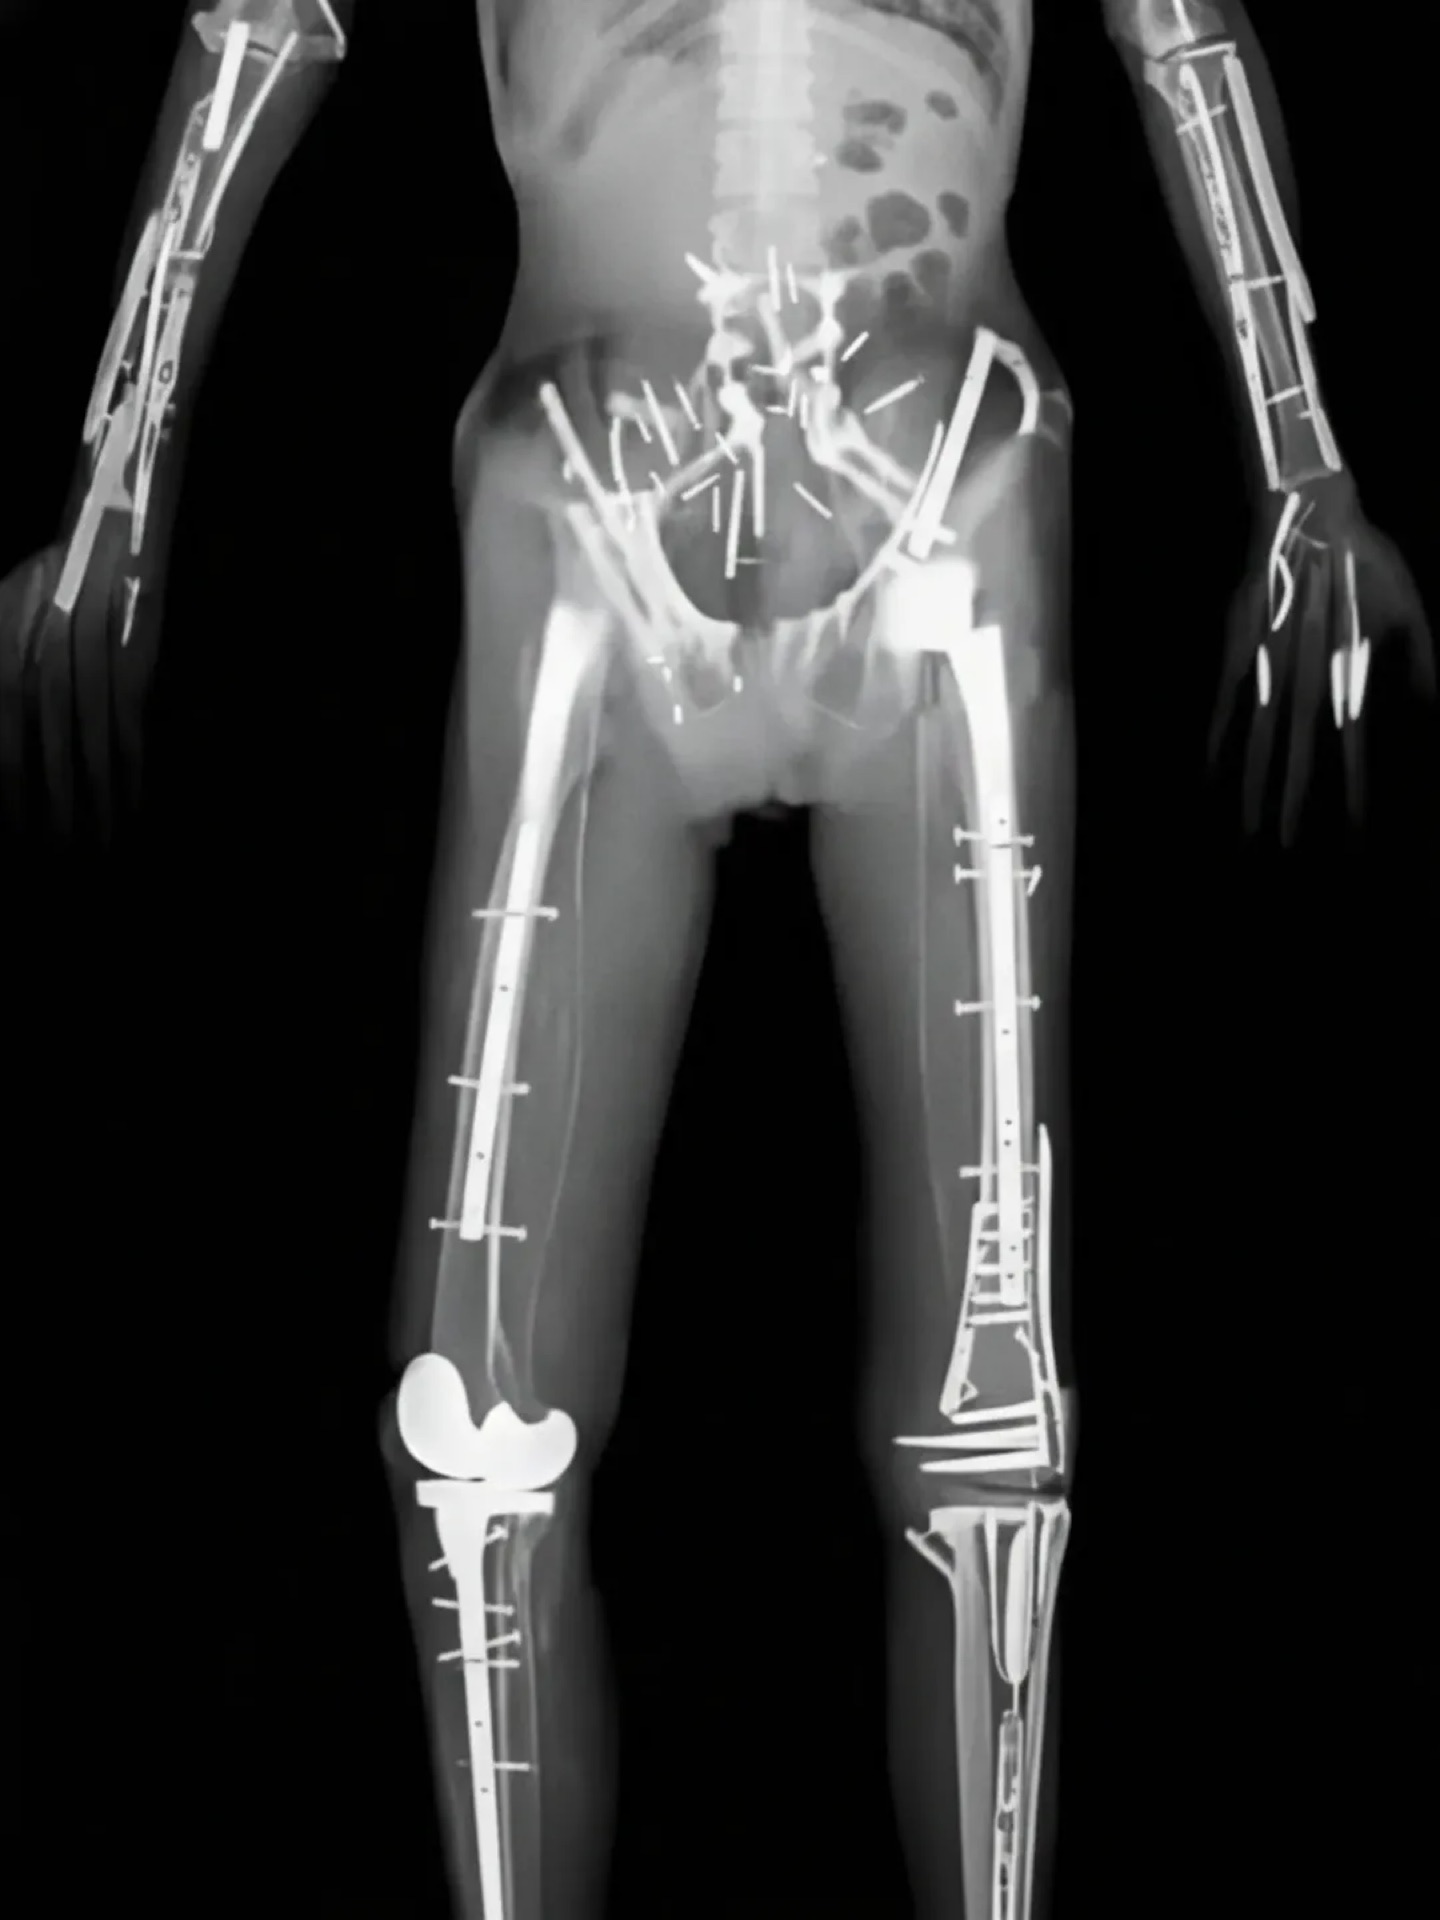

fu6065813.jpg

脚もバシバシよ

>fu6065813.jpg

>脚もバシバシよ

サイボーグじゃん…

骨を全部チタンに変えたらって思いかねないほどボルトと添え木だらけだな…